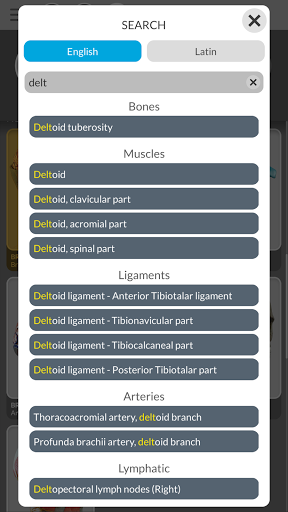

• وظيفة البحث للعثور بسهولة على كل جزء تشريحي

• المصطلحات التشريحية وواجهة المستخدم متوفرة بـ 11 لغة: اللاتينية والإنجليزية والفرنسية والألمانية والإيطالية والبرتغالية والتركية والروسية والإسبانية والصينية واليابانية والكورية

• يمكن عرض المصطلحات التشريحية بلغتين في وقت واحد